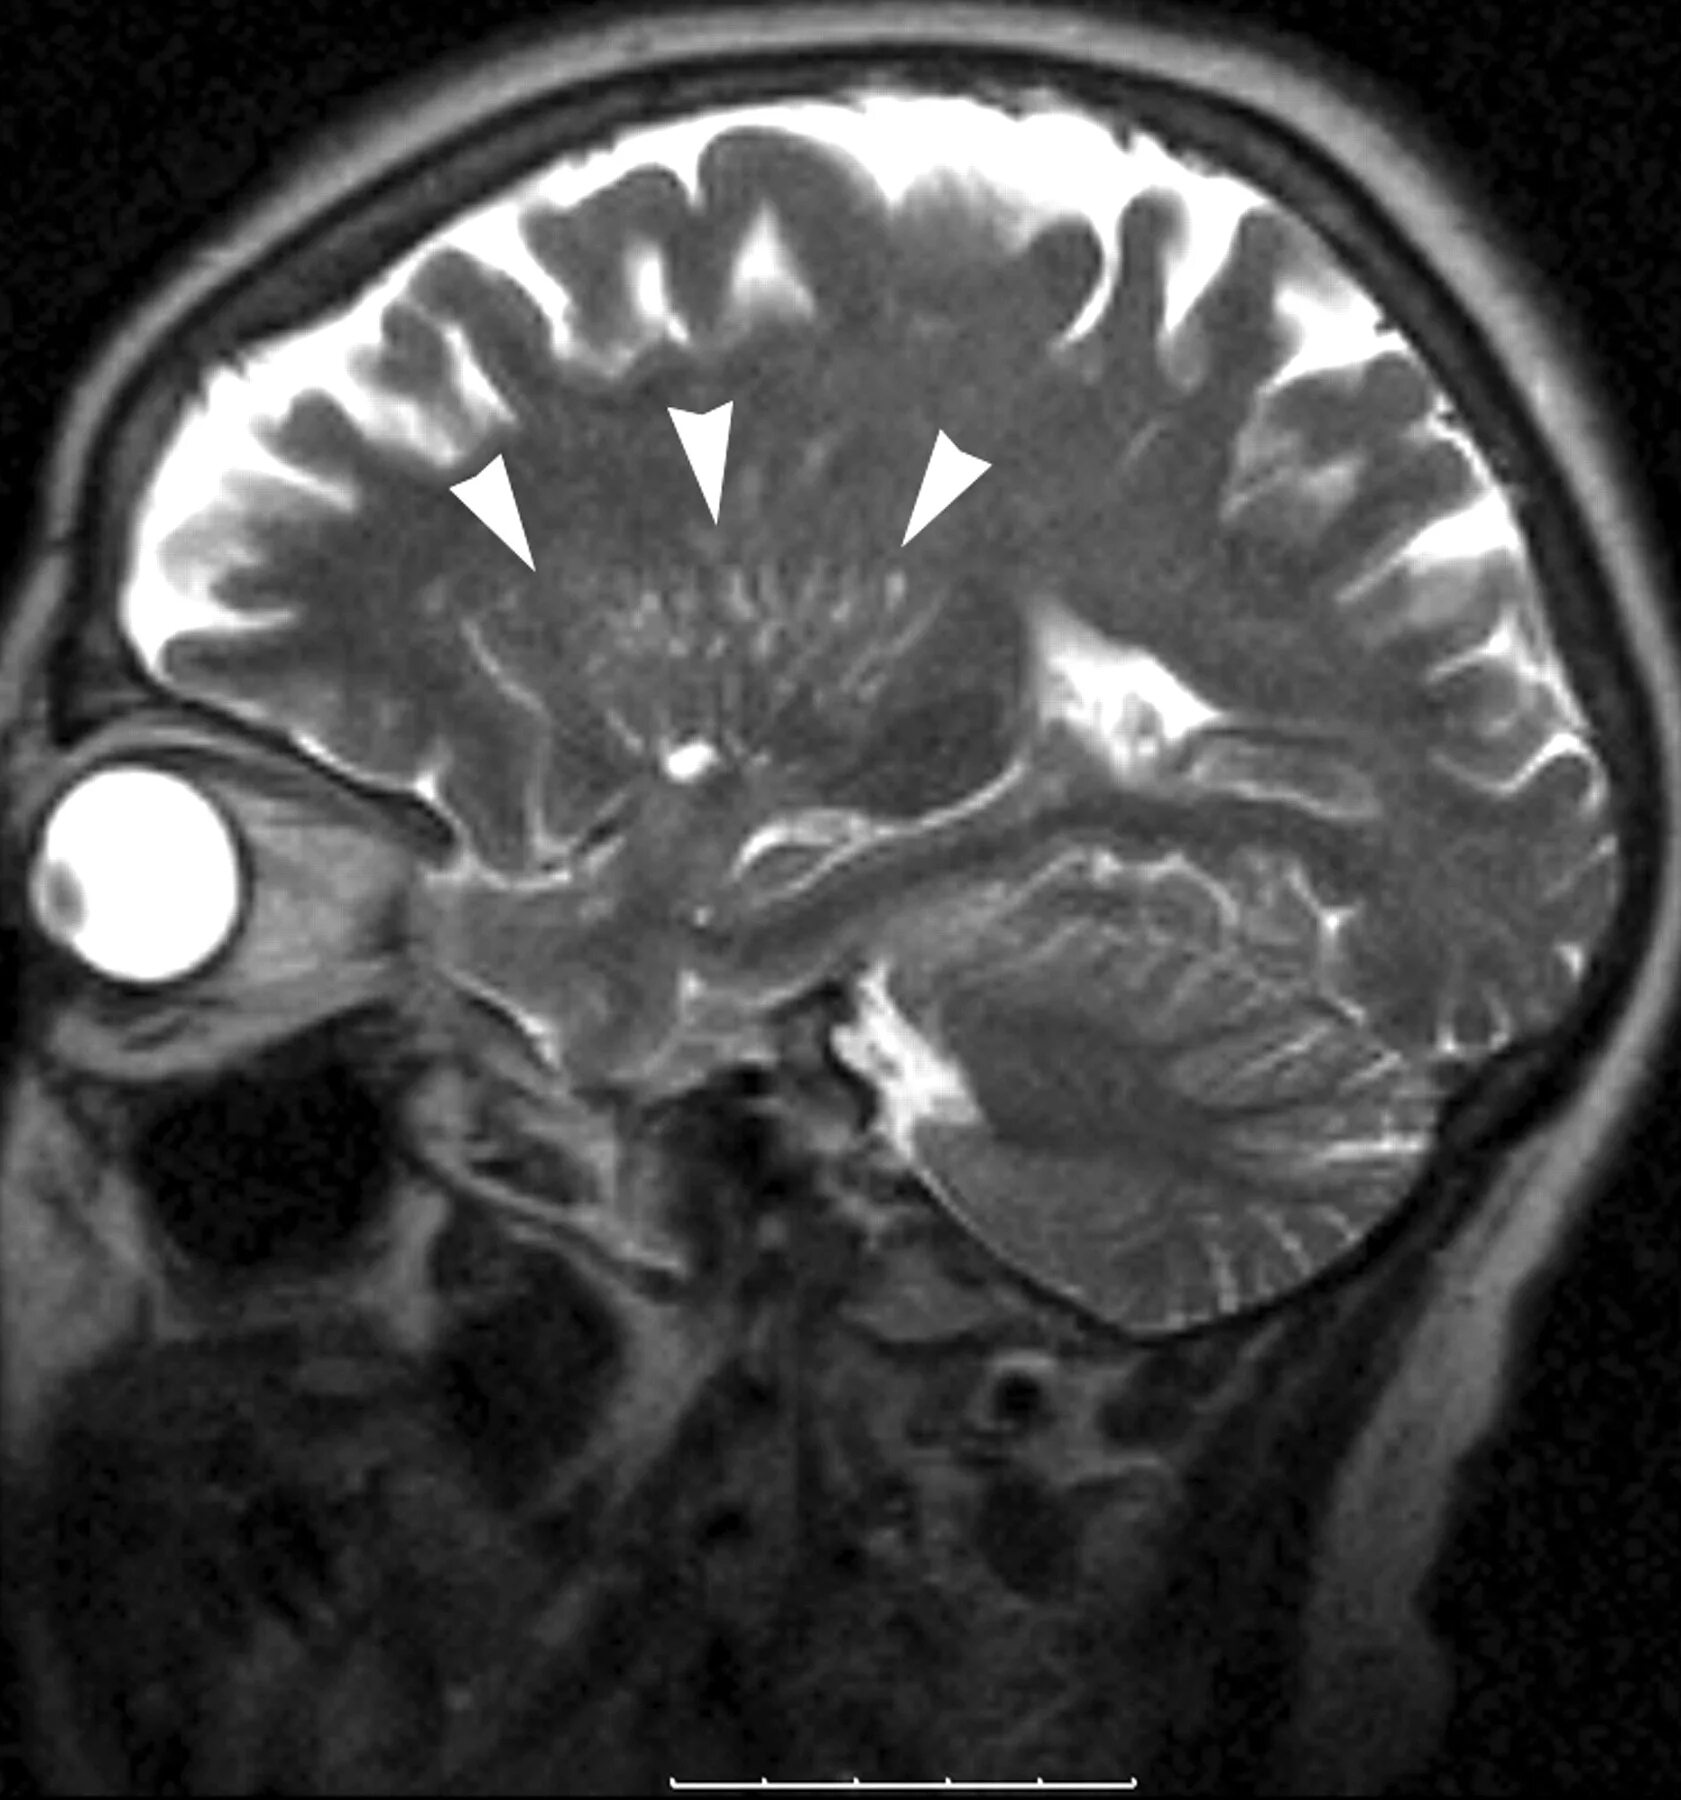

Что значит расширенные периваскулярные пространства